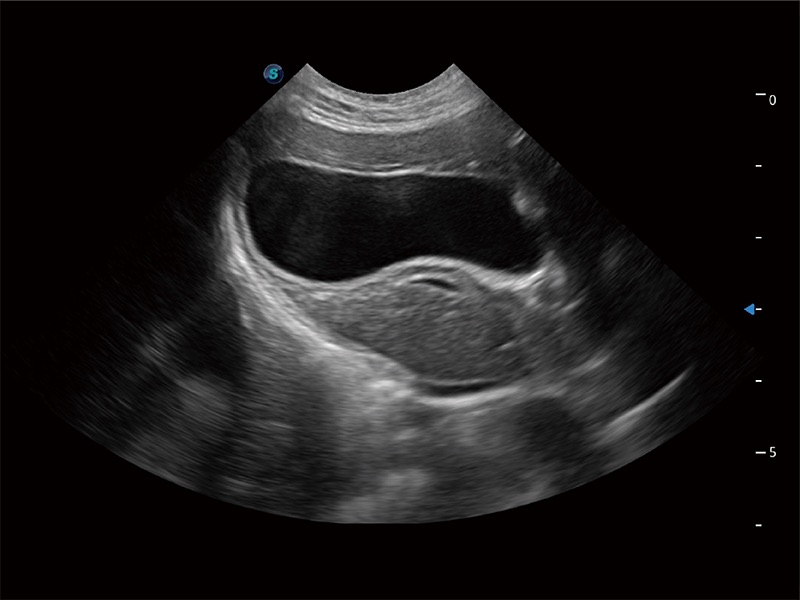

• Auto Bladder 膀胱自动测量

一键自动识别膀胱壁及自动测量膀胱容积,不受膀胱形状和大小的限制,帮助医生快速精准获得测量的数据。